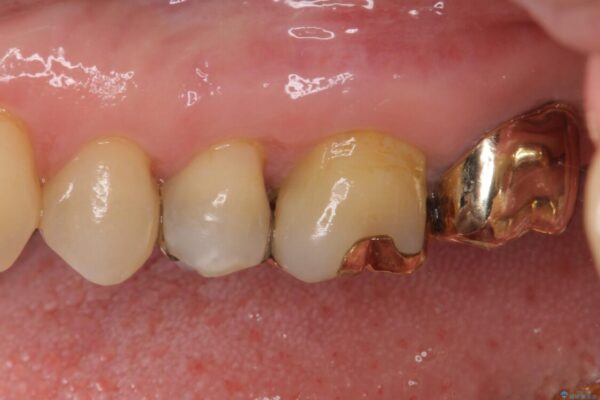

奥歯の銀歯が外れてしまったため、セラミック治療を希望された患者様です。

セラミックインレーによる修復治療を実施しました。

正面から見える場所であったため、セラミックインレーで自然な口元にすることができました。

治療前

• 外れてしまった銀歯 セラミックインレーで自然な仕上がりに 治療前画像